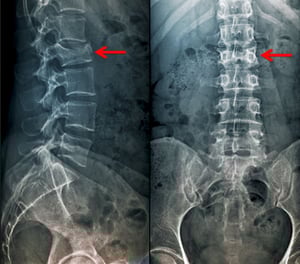

Diese Kompressionsfraktur des 2. Lendenwirbels ist sowohl in der anteroposterioren als auch in der lateralen Ansicht als Höhenverlust der Wirbelkörper sichtbar.

Diese Kompressionsfraktur des 2. Lendenwirbels ist sowohl in der anteroposterioren als auch in der lateralen Ansicht al

Scott Camazine/SCIENCE PHOTO LIBRARY

Diese seitliche Röntgenaufnahme der Wirbelsäule zeigt einen Höhenverlust und eine anteriore Verkeilung aufgrund einer Wirbelkompressionsfraktur.

Diese seitliche Röntgenaufnahme der Wirbelsäule zeigt einen Höhenverlust und eine anteriore Verkeilung aufgrund einer W

Image courtesy of Danielle Campagne, MD.